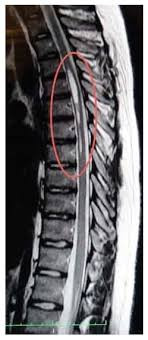

Pencitraan berupa foto rontgen dan CT scan dapat dilakukan untuk mengetahui posisi kelainan tulang, seperti patah tulang. Sementara itu, pemeriksaan magnetic resonance imaging (MRI) dapat dilakukan untuk mencari kerusakan pada sumsum tulang belakang. MRI bisa dilakukan setelah keadaan penderita stabil.